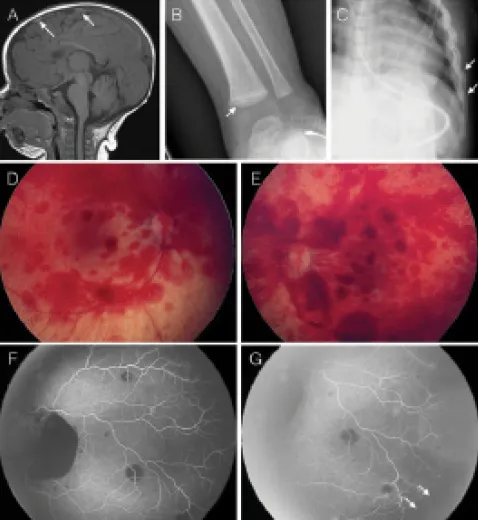

- Abusive Head Trauma (AHT): subdural hematoma, retinal hemorrhages.

- Subdural hemorrhage (interhemispheric fissure).

- Widespread, multi-layered retinal hemorrhages.

⭐ Classic Triad of AHT: Encephalopathy, Subdural Hemorrhage, and Retinal Hemorrhages.

⭐ Retinal hemorrhages are highly specific for Abusive Head Trauma (AHT), but their absence does not rule it out.